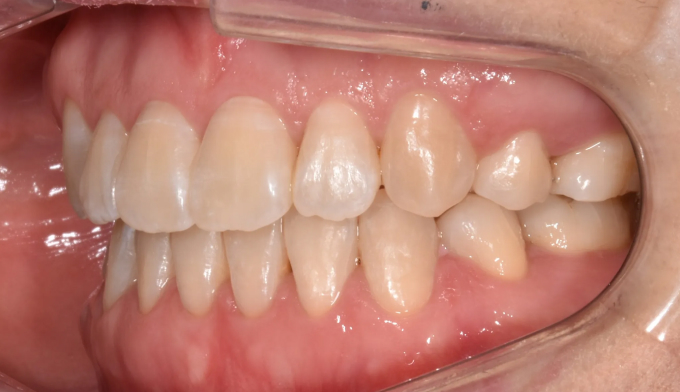

돌출입과 개방교합이 동시에 있는 경우에는 발치교정을 통해 앞니를 넣어주면 개방교합이 쉽게 개선됩니다. 이때 주의할점은 미소시 치아의 노출정도입니다. 또한 개방교합의 경우에는 재발 경향이 높기 때문에 주기적인 경과관찰이 필요하며 최종위치에 안정적으로 치아가 위치해있다고 판단이 들었을 때 교정치료를 종료하여야 합니다.

총 교정기간은 25개월입니다.